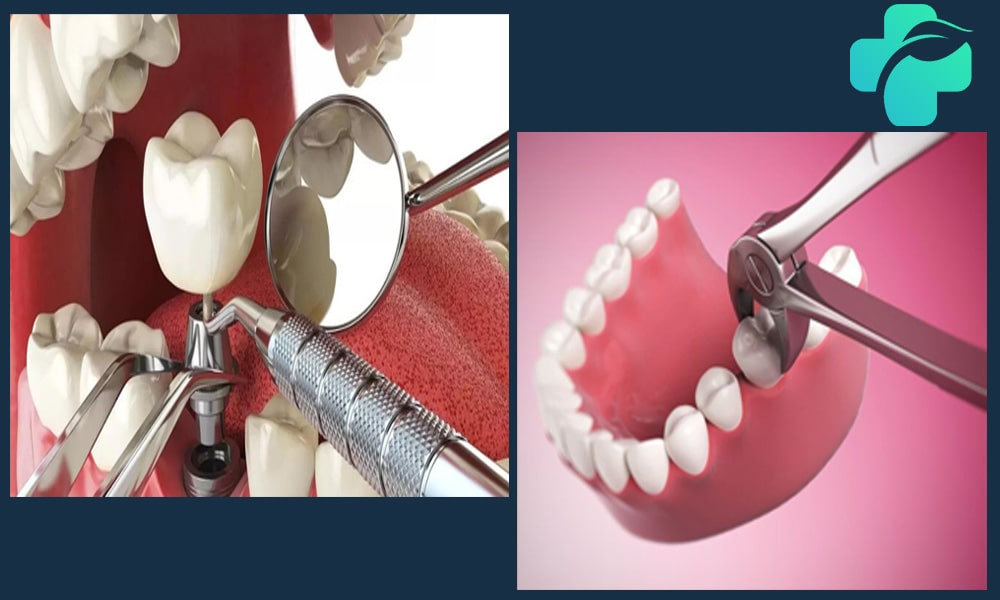

چه مدت بعد از کشیدن دندان می توان ایمپلنت کاشت؟ بررسی زمان کاشت ایمپلنت بعد از کشیدن دندان

مدت زمان لازم برای کاشت ایمپلنت پس از کشیدن دندان به میزان ترمیم استخوان و بافت لثه بستگی دارد. در بعضی موارد میتوان ایمپلنت را بلافاصله پس از کشیدن دندان انجام داد، ولی در شرایطی که نیاز به بازسازی بافت یا پیوند استخوان وجود دارد، چند ماه انتظار لازم است. برنامهریزی دقیق زمان کاشت، همراه با رعایت مراقبت های بعد از کشیدن دندان، تضمین کننده اتصال موفق ایمپلنت به استخوان و کاهش خطر عوارض است.

زمان کاشت ایمپلنت بعد از کشیدن دندان

در کل، چهار نوع بازه زمانی برای انجام ایمپلنت پس از کشیدن دندان می توان در نظر گرفت که هر کدام مزایا و محدودیت های خاص خود را دارند: